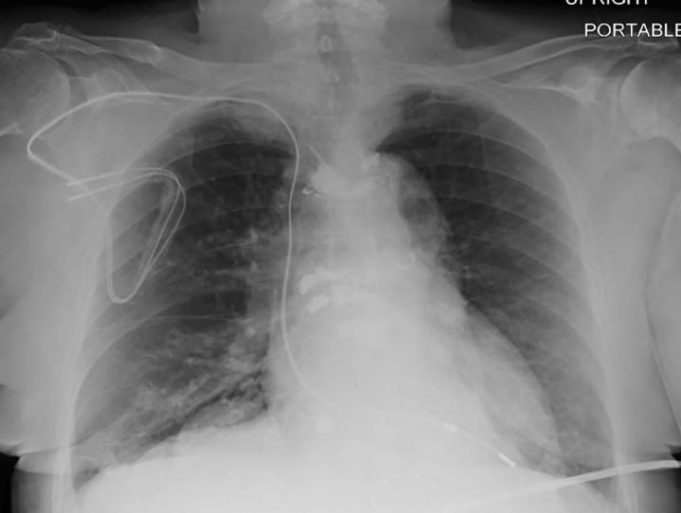

This advertorial has been sponsored by Boston Scientific

Two landmark studies have been published in 2020 following the use of subcutaneous implantable cardioverter defibrillator (S-ICDs) as a primary prevention therapy for sudden cardiac death. Cardiac Rhythm News speaks to the...